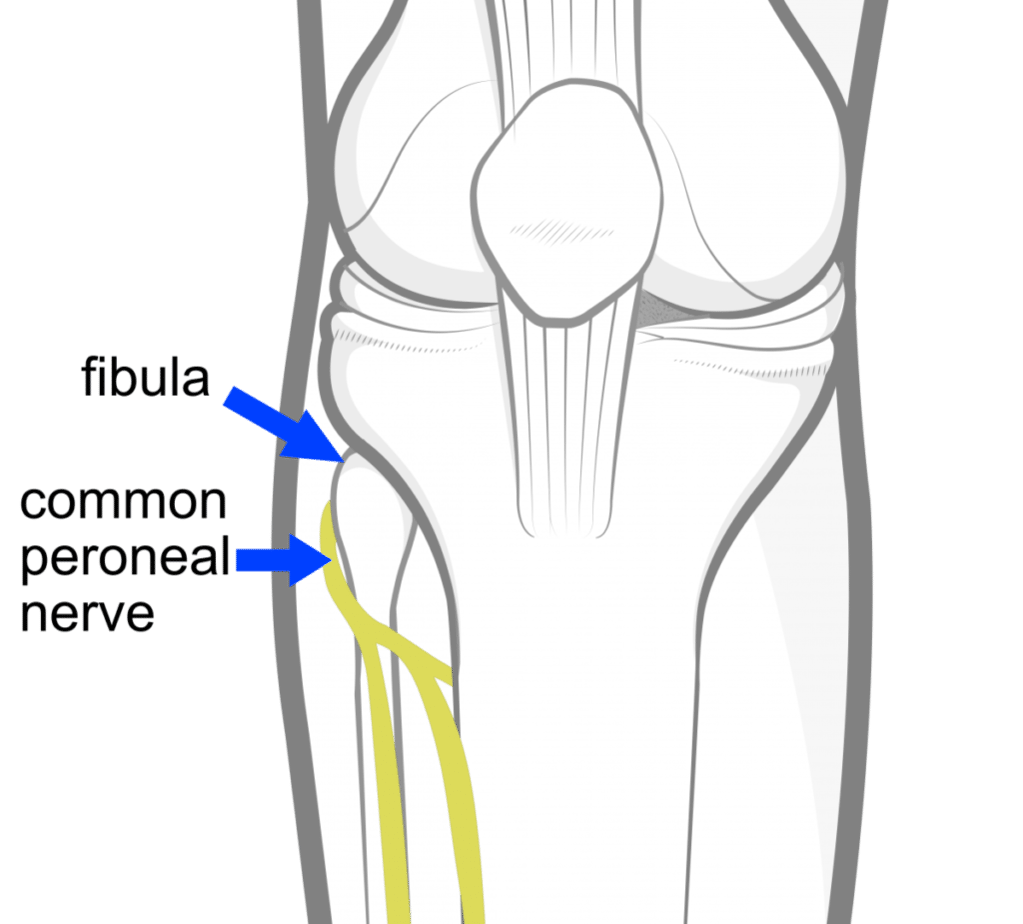

Common Fibular Nerve Anatomy – pediagenosis